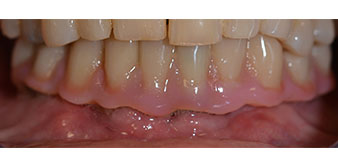

Tras esto, se realizan la impresión y el registro de la mordida para que el protésico dental pueda empezar inmediatamente con la elaboración de la prótesis provisional, cuya implantación se realiza el mismo día (figs. 17 y 18).

Implantes

Fig. 17

Fig. 18